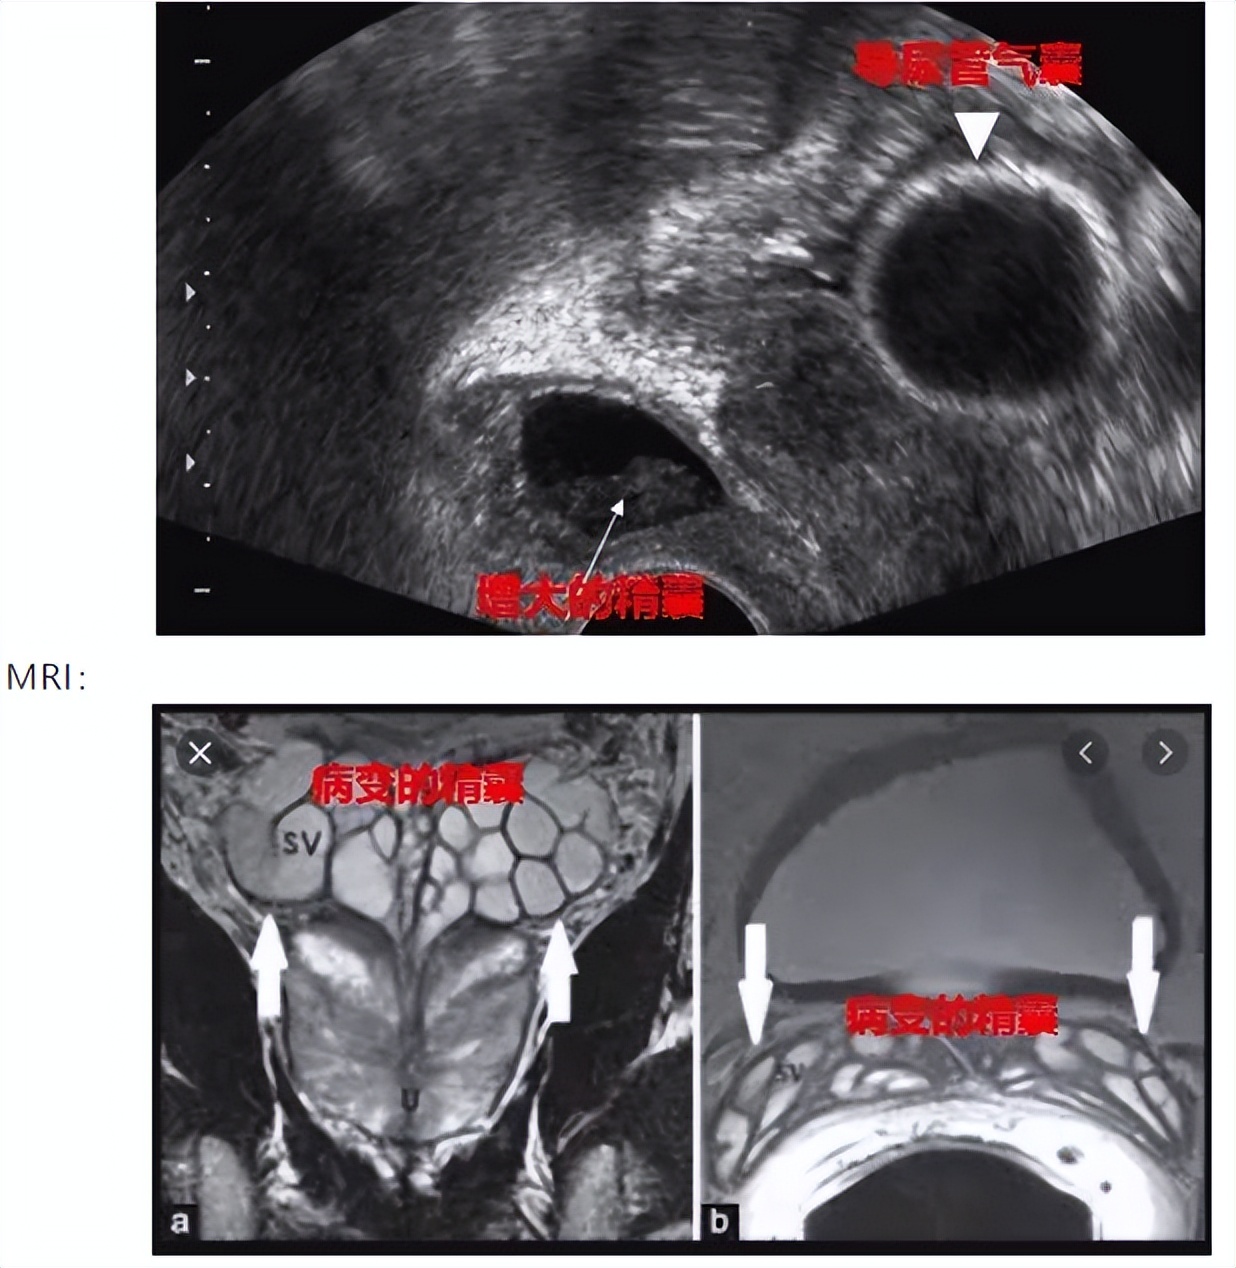

持续性血精: 持续存在(超过1个月)原因不明的血精,经直肠超声是首选的影像学检查。可识别前列腺、精囊和精索的结构性异常,如有疑似异常时引导活检。

MRI(特别是直肠内线圈MRI): 是二线影像学检查手段,当经直肠超声检查技术上不充分或者无法确诊时可选用。